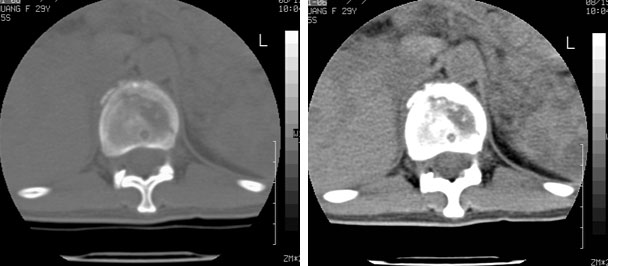

车祸致t12压缩性骨折,行ct扫描意外发现椎体多发肿瘤样病变,建议加拍骨盆平片,患者平常无症状。

考虑多发骨髓瘤可能性大。(骨松质内弥漫性分布,边缘清晰的溶骨性破坏,无硬化。睥脏增大,其内有多个圆形底密度影。淋巴瘤不除。

脾脏及椎体多发占位病变。首先考虑淋巴瘤,其次骨髓瘤。建议查本周氏蛋白

1:胸腰椎多发破坏伴骨折,近似穿凿样,考虑骨髓瘤,但有好多不符只出1、发病年龄小、女性,2、病变似有硬化环。2:淋巴瘤可能性大,骨及脾脏均有改变(脾脏改变似与外伤关系不大)建议密切结合临床及相关检验进一步诊断,期待结果。

椎体多发性溶骨性破坏,部分融合,椎旁无软组织肿块、椎间隙正常,t12 压缩,脾脏增大,其内示多发低密度影,首先考虑多发性骨髓瘤。病人较年轻,平素无异常,转移瘤可能性小。